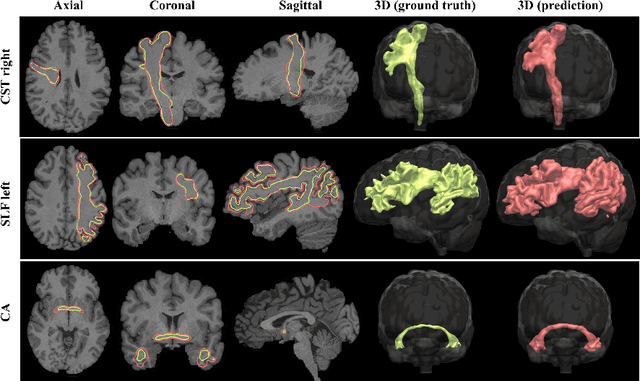

Abstract:While the major white matter tracts are of great interest to numerous studies in neuroscience and medicine, their manual dissection in larger cohorts from diffusion MRI tractograms is time-consuming, requires expert knowledge and is hard to reproduce. In previous work we presented tract orientation mapping (TOM) as a novel concept for bundle-specific tractography. It is based on a learned mapping from the original fiber orientation distribution function (fODF) peaks to tract specific peaks, called tract orientation maps. Each tract orientation map represents the voxel-wise principal orientation of one tract.Here, we present an extension of this approach that combines TOM with accurate segmentations of the tract outline and its start and end region. We also introduce a custom probabilistic tracking algorithm that samples from a Gaussian distribution with fixed standard deviation centered on each peak thus enabling more complete trackings on the tract orientation maps than deterministic tracking. These extensions enable the automatic creation of bundle-specific tractograms with previously unseen accuracy. We show for 72 different bundles on high quality, low quality and phantom data that our approach runs faster and produces more accurate bundle-specific tractograms than 7 state of the art benchmark methods while avoiding cumbersome processing steps like whole brain tractography, non-linear registration, clustering or manual dissection. Moreover, we show on 17 datasets that our approach generalizes well to datasets acquired with different scanners and settings as well as with pathologies. The code of our method is openly available at www.github.com/MIC-DKFZ/TractSeg.

Abstract:The individual course of white matter fiber tracts is an important key for analysis of white matter characteristics in healthy and diseased brains. Uniquely, diffusion-weighted MRI tractography in combination with region-based or clustering-based selection of streamlines allows for the in-vivo delineation and analysis of anatomically well known tracts. This, however, currently requires complex, computationally intensive and tedious-to-set-up processing pipelines. TractSeg is a novel convolutional neural network-based approach that directly segments tracts in the field of fiber orientation distribution function (fODF) peaks without requiring tractography, image registration or parcellation. We demonstrate in 105 subjects from the Human Connectome Project that the proposed approach is much faster than existing methods while providing unprecedented accuracy. The code and data are openly available at https://github.com/MIC-DKFZ/TractSeg/ and https://doi.org/10.5281/zenodo.1088277, respectively.

Abstract:While the major white matter tracts are of great interest to numerous studies in neuroscience and medicine, their manual dissection in larger cohorts from diffusion MRI tractograms is time-consuming, requires expert knowledge and is hard to reproduce. Tract orientation mapping (TOM) is a novel concept that facilitates bundle-specific tractography based on a learned mapping from the original fiber orientation distribution function (fODF) peaks to a list of tract orientation maps (also abbr. TOM). Each TOM represents one of the known tracts with each voxel containing no more than one orientation vector. TOMs can act as a prior or even as direct input for tractography. We use an encoder-decoder fully-convolutional neural network architecture to learn the required mapping. In comparison to previous concepts for the reconstruction of specific bundles, the presented one avoids various cumbersome processing steps like whole brain tractography, atlas registration or clustering. We compare it to four state of the art bundle recognition methods on 20 different bundles in a total of 105 subjects from the Human Connectome Project. Results are anatomically convincing even for difficult tracts, while reaching low angular errors, unprecedented runtimes and top accuracy values (Dice). Our code and our data are openly available.

Abstract:The state-of-the-art method for automatically segmenting white matter bundles in diffusion-weighted MRI is tractography in conjunction with streamline cluster selection. This process involves long chains of processing steps which are not only computationally expensive but also complex to setup and tedious with respect to quality control. Direct bundle segmentation methods treat the task as a traditional image segmentation problem. While they so far did not deliver competitive results, they can potentially mitigate many of the mentioned issues. We present a novel supervised approach for direct tract segmentation that shows major performance gains. It builds upon a stacked U-Net architecture which is trained on manual bundle segmentations from Human Connectome Project subjects. We evaluate our approach \textit{in vivo} as well as \textit{in silico} using the ISMRM 2015 Tractography Challenge phantom dataset. We achieve human segmentation performance and a major performance gain over previous pipelines. We show how the learned spatial priors efficiently guide the segmentation even at lower image qualities with little quality loss.